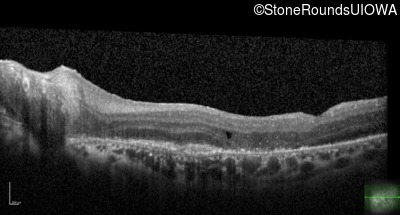

This 43 year old woman first experienced a slight loss of visual acuity at age 23. Fluorescein angiography at that time revealed some vascular leakage from the optic discs and peripheral retina. The maximum combined response of the ERG revealed a selective loss of the b-wave.

Age at visit: 43 years (Visit 2)